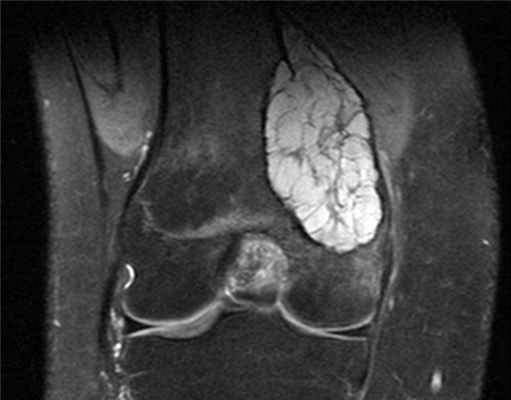

Аневризматические кисты кости обычно возникают до 25-летнего возраста, и причина их не выяснена. Эти кисты состоят из множества наполненных кровью полостей, которые размещены группами. Такие кисты обычно возникают вблизи внутренних краев длинных костей (плечевой и бедренной кости), но могут возникать практически в любой кости. Эти кисты, как правило, растут медленно. Часто наблюдаются боль и отек. До постановки диагноза киста может существовать от нескольких недель до года.

Для диагностики аневризматических костных кист запястья врачи обычно проводят рентгенологическое исследование Рентгенологическое исследование Зачастую врач может диагностировать костно-мышечное заболевание на основании анамнеза и по результатам физикального осмотра. Чтобы облегчить постановку или подтверждение диагноза, иногда необходимы. Прочитайте дополнительные сведенияХирургическое удаление всей кисты является наиболее результативным видом лечения, но иногда наблюдается ее рецидив, особенно при неполном удалении кисты. Лучевой терапии следует по возможности избегать, поскольку в дальнейшем возможно развитие злокачественных опухолей. Однако лучевая терапия Лучевая терапия для лечения онкологического заболевания Радиация является формой интенсивной энергии, генерируемой радиоактивным веществом, таким как кобальт, или специализированным оборудованием, например (линейным) ускорителем атомных частиц. Облучение. Прочитайте дополнительные сведения может быть показана для лечения кист позвоночника, не подлежащих хирургическому лечению и сдавливающих спинной мозг.

Различают две формы аневризмальных костных кист: центральную и эксцентрическую. В течении болезни выделяют такие же фазы, как и при солитарных кистах. Клинические проявления достигают максимума в фазе остеолиза, постепенно уменьшаются в фазе отграничения и исчезают в фазе восстановления. На рентгенограммах в фазе остеолиза выявляется бесструктурный очаг с внекостным и внутрикостным компонентом, при эксцентричных кистах внекостная часть по размеру превышает внутрикостную. Надкостница всегда сохранена. В фазе отграничения между внутрикостной зоной и здоровой костью образуется участок склероза, а внекостная зона уплотняется и уменьшается в размере. В фазе восстановления на рентгенограммах обнаруживается участок гиперостоза или остаточная полость.